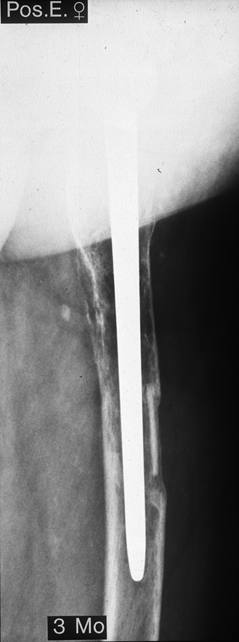

Fallbeispiel

Weiblich, 78 Jahre. Die

Bilder zeigen eine deutlich gelockerte zementierte

Hüftprothese. Der Knochen um den Zement ist stellenweiße

papierdünn

Zustand nach Austausch der

zementierten Prothese durch eine Bicon-Pfanne sowie

einen SLR-Schaft.

Die Röntgenbilder zeigen das Ergebniss nach 13 Jahren.

Die nun 91 jährige Patientin ist gut gehfähig und völlig